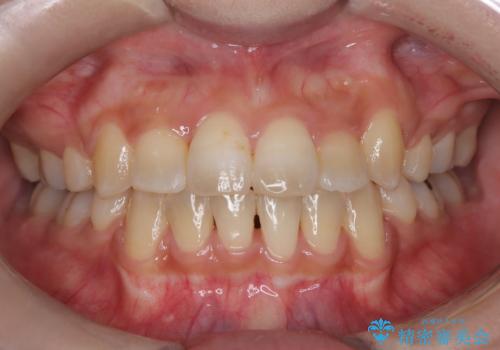

[ マウスピース矯正治療 ] がたつき ねじれのある前歯をきれいにしたい

![[ マウスピース矯正治療 ] がたつき ねじれのある前歯をきれいにしたいの症例 治療前](https://seimitsushinbi.jp/wp/wp-content/uploads/2025/04/8438e7299f1b9566ac213e8e9f7db5f6-500x350.jpg?v=1745226068)